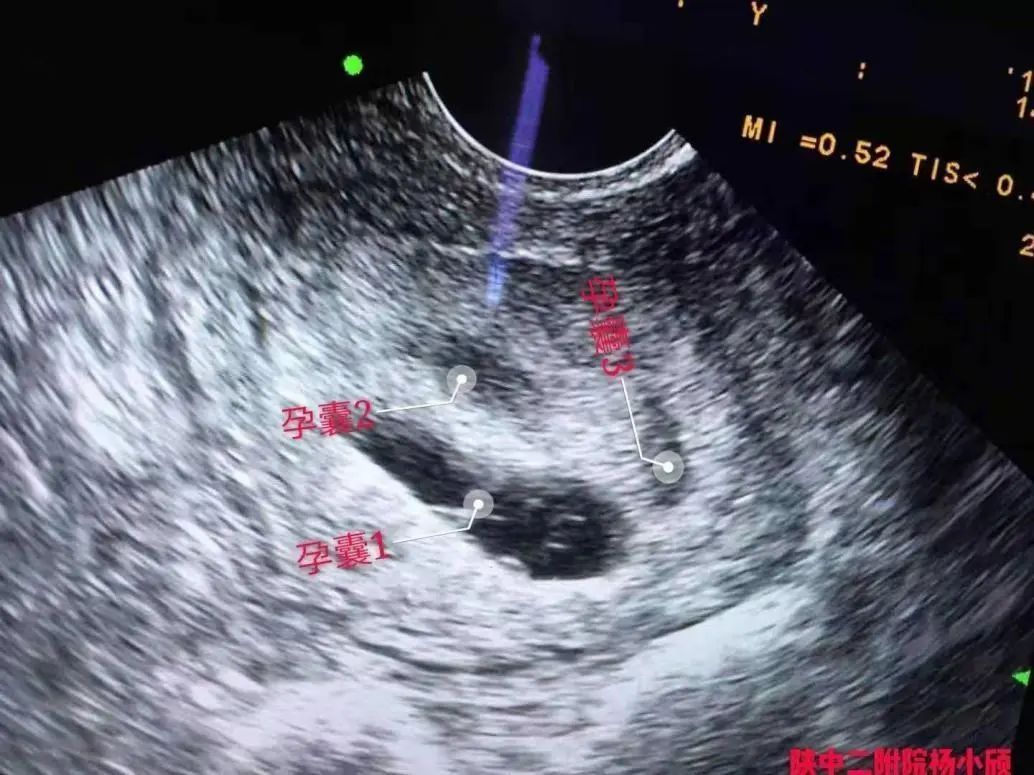

当时移植了2个胚胎,可是现在做彩超有3个孕囊!医生说,是因为1个胚胎又分裂成了2个!

术前超声

看着患者恳求的目光,杨小颀一边鼓励安慰,一边邀请到超声科主任杨兵社进行会诊,确定患者分裂的胚胎为双绒双羊。双绒双羊就是双绒毛膜双羊膜囊,不是两个宝宝共用一个胎盘,就是双卵双胎,两个宝宝分别在自己的羊膜腔内。这种情况,一般多数是两个卵,两个胚胎,也有一个卵两个胚胎的情况,但是是少数。